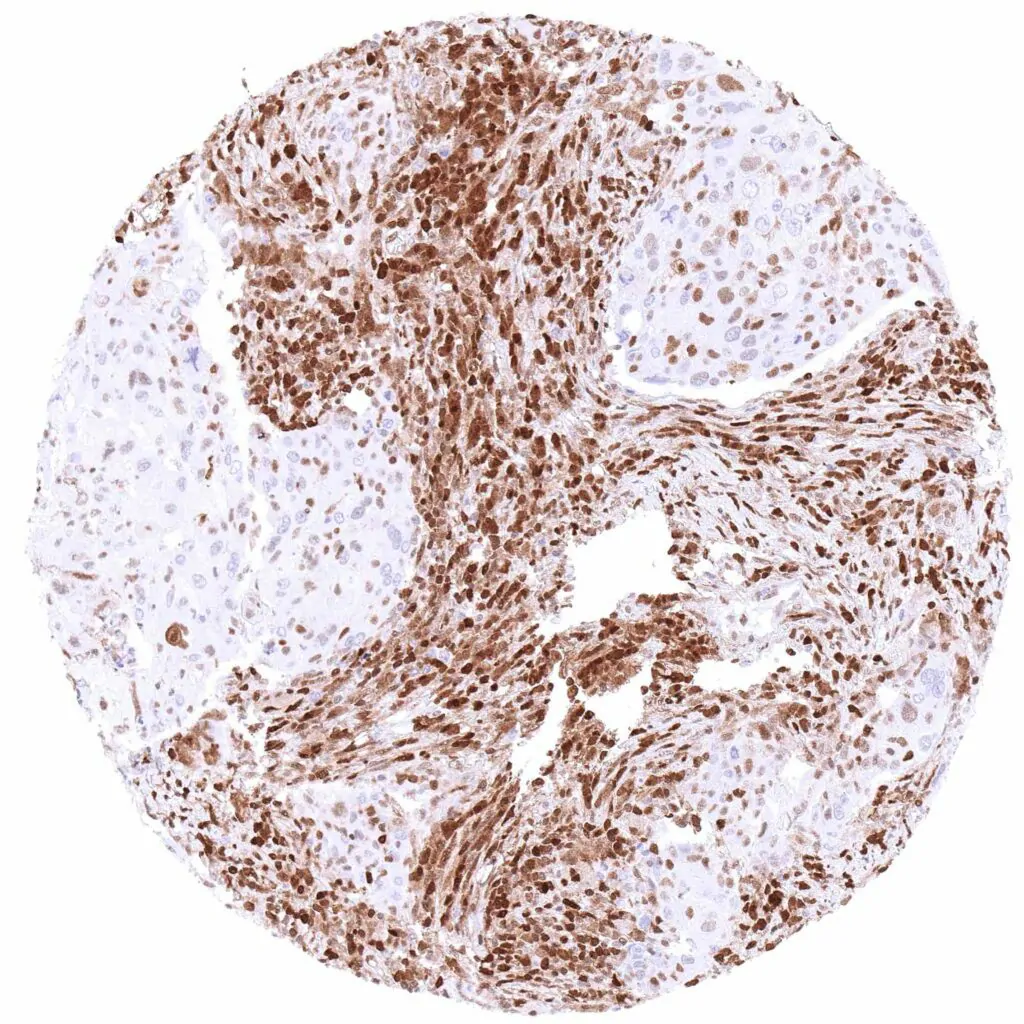

Ovary – Malignant mixed Mullerian tumor with strong, predominantly nuclear p27 staining of a large subset of tumor cells.